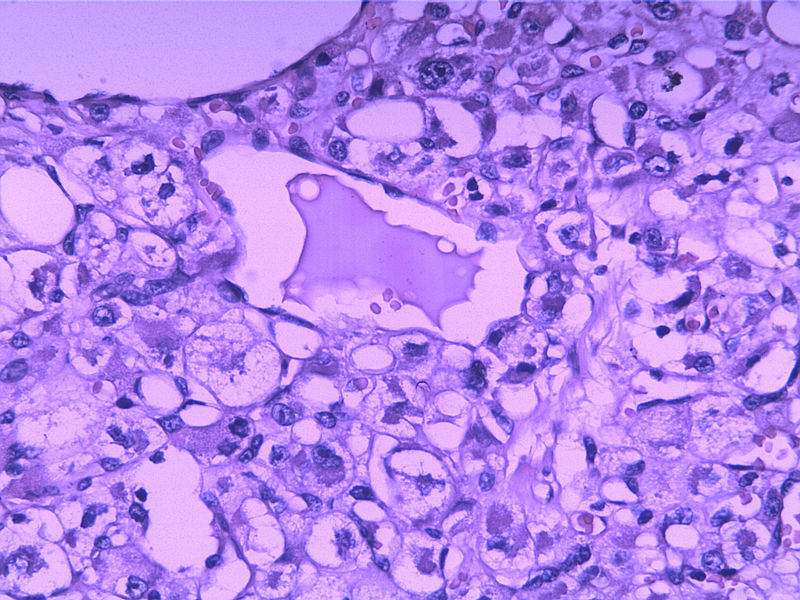

女30Y,大腿肿物5Y,直径3cm

• 女30Y,大腿肿物5Y,直径3cm图2

图2

Micro description

● Well circumscribed but non-encapsulated with infiltrative borders

● At least focal typical liposarcomatous areas

● Pleomorphic cells cover > 65% of cut surface with MFH-like, round cell liposarcoma-like (without vascular network), spindle cell liposarcoma-like or epithelioid cells (Mod Path 1999;12:722)

● Usually high grade with enlarged round to bizarre nuclei; tumor necrosis common; median 25 mitotic figures/10 HPF

● May have neutrophils within giant cells, hemangiopericytic foci, extra- and intracellular hyaline droplets

本例可能是具有非典型性组织学特征的腺泡状软组织肉瘤

Enzinger and Weiss:The individual cells are large, rounded, or more often polygonal and display little variation in size and shape. They have distinct cell borders and one or more vesicular nuclei with small nucleoli and abundant granular, eosinophilic, and sometimes vacuolated cytoplasm. Mitotic figures are scarce. Rare pleomorphic tumors have been reported in the literature ——Evans HL: Alveolar soft-part sarcoma. A study of 13 typical examples and one with a histologically atypical component.  Cancer  1985; 55:912.

腺泡状软组织肉瘤的边缘常看见扩张的静脉,并常见脉管浸润,很类似于副节瘤或血管周细胞瘤